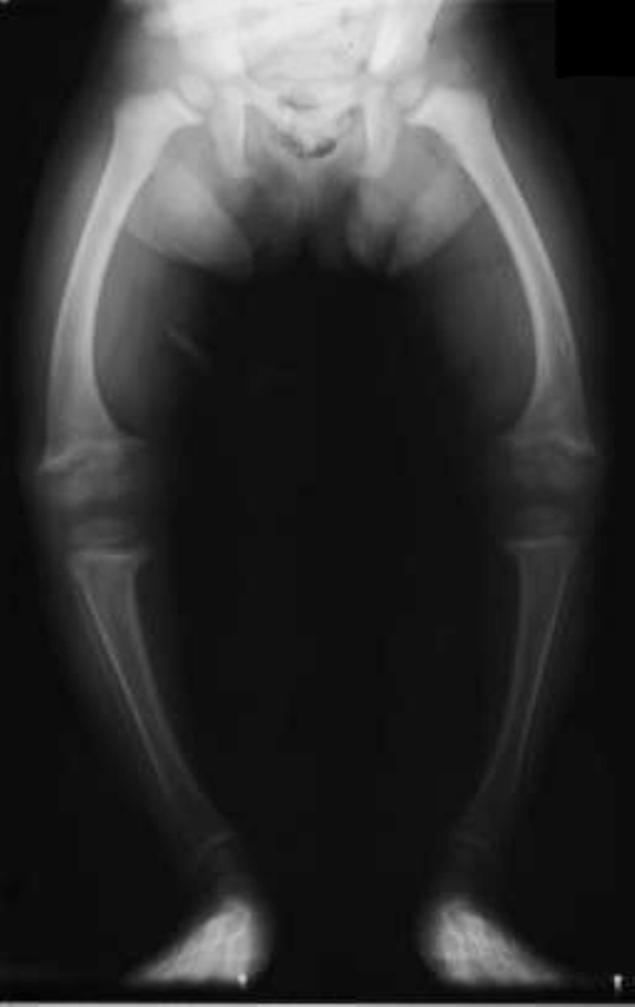

Încă şi mai îngrijorător (şi, din nou, paradoxal) e faptul că maladii considerate în trecut boli ale sărăciei au schimbat tabăra, fiind azi pe cale să devină boli ale abundenţei. Un exemplu frapant este rahitismul, care în secolul al XIX-lea şi începutul secolului XX era o boală răspândită în rândul populaţiei sărace din mahalalele marilor oraşe industriale ale Europei. Prost hrăniţi şi insuficient expuşi soarelui (din cauză că o pătură groasă de fum negru acoperea cerul, ca rezultat al activităţii uzinelor alimentate cu cărbuni), copiii din aceste medii sufereau în mare proporţie de această boală ce producea deformări vizibile, uneori invalidante, ale scheletului.

Şi iată că azi rahitismul se întoarce, de data acesta pentru a lovi copiii care îşi petrec o mare parte a timpului în casă, în faţa computerului ori a televizorului, lipsiţi de binefacerile soarelui. Nu mai e vorba despre copii săraci, din medii defavorizate, ci despre copii din familii cu o situaţie materială bună. Dar efectele bolii sunt aceleaşi ca şi în trecut.